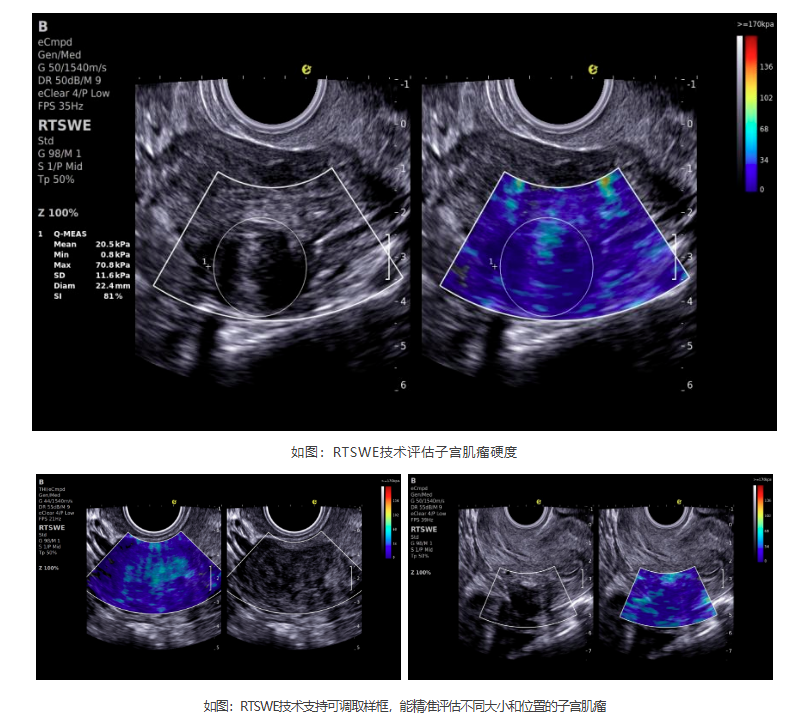

如今,百乐博平台医疗ePascal东风系列搭载的RTSWE?实时E成像技术为肌瘤良恶性的鉴别带来了突破!该技术基于OmniSound? 平面波超快速平台,以25000帧/秒的采集帧频,实现最小0.4mm病灶的精准硬度测量。它犹如为超声检查赋予"智能触诊"能力,通过定量分析组织硬度,辅助判断肌瘤性质:

cd2301cd65513af0501835669682402.png